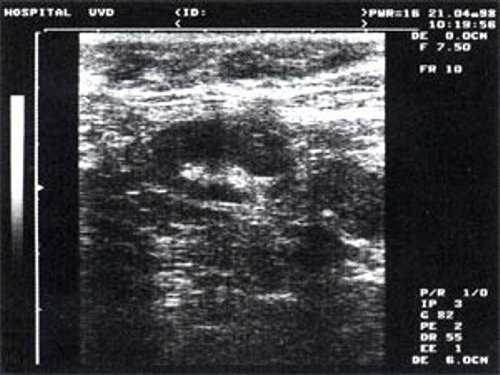

При повторных УЗ осмотрах на фоне массированной противовоспатительной терапии было отмечено увеличение числа лимфатических узлов вовлеченных в процесс активизации. При этом заметной перестройки эхоструктуры и уменьшения размеров в наблюдаемых лимфатических узлах отмечено не было (рис 4).

Рис. 4. Варианты изображения увеличенного лимфатического узла с УЗ-признаками доброкачественной аденопатии у больного с синдромом иммунодефицита.